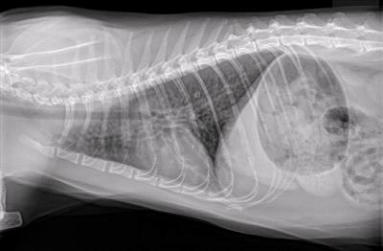

Lungs of a kitty with asthma